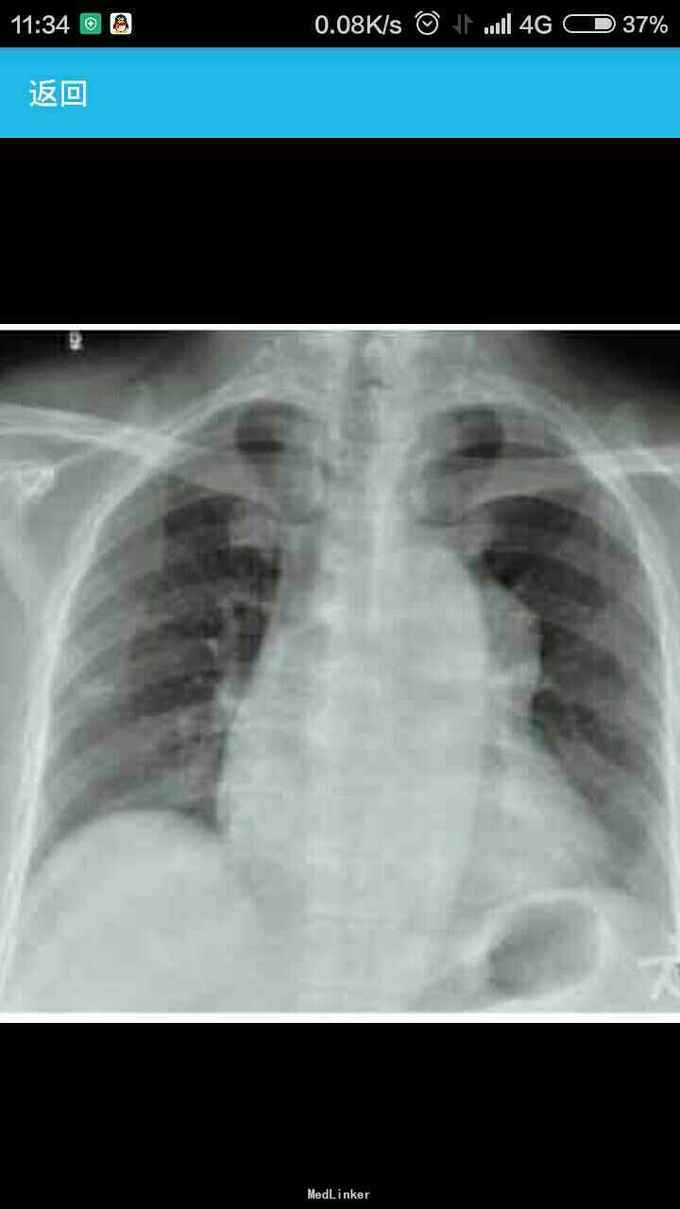

女性,60岁,因左 趾关节红肿、剧痛,红肿弥漫足背 23天来诊,不伴发热,无外伤史, 全身体检无明显异常。 胸片示,左侧前上纵隔占位性病变(图1)。胸部CT示,左侧前上纵隔内见5.7 cm×3.8 cm软组织肿块影,内见斑片状稍高密度影,境界不清(图2——5)。 实验室检查显示,血尿酸517.1 μmol/L(正常值180——357 μmol/L),临床诊断为“急性痛风”,为排除相关疾病作进一步检查。 印象:左侧前上纵隔占位(恶性肿瘤?畸胎瘤?)。 手术结果:肿瘤位于左前纵隔,大小约为8 cm×8 cm ×6 cm,质硬,表面光滑,与心包、无名静脉、肺门粘连(侵犯壁层、脏层、胸膜、肺门、心包、膈肌、膈神经,伴肿大淋巴结)。【病理结果示】(图6):肿块9 cm×6 cm×4 cm,侵犯周围脂肪组织,伴神经内分泌分化。肿块标记:CD5(+)、CD117(+)、嗜铬粒蛋白A(CgA)灶(+)、突触素(Syn,+)、CD56 (-)、细胞增殖因子Ki-67约20%(+)。【诊断】胸腺鳞状细胞癌Ⅱ——Ⅲ级,伴神经内分泌分化。